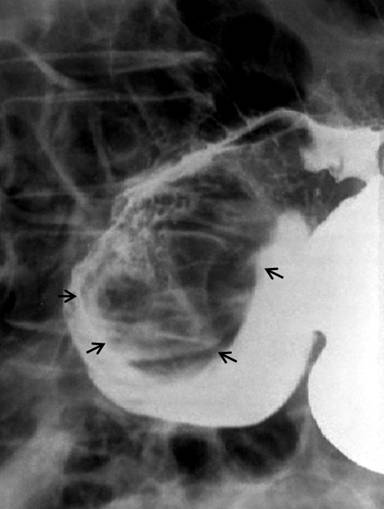

Figure 4. Barium study showing a well-defined lobular filling defect with smooth outline (arrows) in the first part of the duodenum. |

|

Abdominal ultrasonography showed a distended gallbladder without any calculi, prominent intrahepatic biliary radicals, a (10 mm) common bile duct dilated to the lower end with no calculi, prominent main pancreatic duct and a 2.8x1.9 cm hypoechoic mass near the distal end of the common bile duct. An abdominal computed tomography (CT) scan confirmed the dilatation of the common bile duct and the main pancreatic duct, and revealed an ill-defined hypodense mass 6.5x5.5 cm in size arising from the uncinate process of the pancreas (Figure 1). The mass involved the duodenum with an extension to the duodenojejunal flexure. The proximal duodenum was found to be dilated. The CT scan suggested the diagnosis of a pancreatic mass with duodenal infiltration. Upper gastrointestinal endoscopy was performed showing esophagitis and extraneous compression in the duodenal bulb. A side view endoscopy was performed and showed a long pedicle-like structure extending from the duodenal bulb into the distal duodenum along the medial wall of the second part of the duodenum (Figure 2). The distal end of this structure, the ampulla and the distal duodenal lumen could not be visualized. An attempt was made to pull the distal end of the structure using biopsy forceps but without success. Besides these findings, no ulcers, strictures or growths were found in the duodenum. In view of the endoscopic findings, the CT scan was again reviewed. The mass initially described as originating from the uncinate process was suspected to be intraluminal within the distal duodenum with a smooth outline at the distal end. However, this mass could not be defined as separate from the pancreas. In addition, a characteristic sign of “duodenal wall invagination” was observed in the dilated first part of the duodenum (Figure 3). Barium meal examination of the upper digestive tract showed a well defined smooth lobular filling defect in the dilated first part of the duodenum (Figure 4). Given the above findings, a duodenal polypoid mass of unknown nature was suspected. A side view endoscopy was repeated and endoscopic ultrasonography (EUS) was also performed. During this examination, a large polypoid mass with normal overlying mucosa was seen in the proximal duodenum (Figure 5a). The ampulla was seen as separate from the polyp and was found to be normal as was the visualized distal duodenum (Figure 5b). Endoscopic ultrasonography revealed a homogenous echogenic mass occupying the submucosa in the duodenal bulb with a normal pancreas which was not involved by the mass (Figure 5c). A biopsy taken from the polyp showed non-specific changes in the mucosa.

They are usually asymptomatic and are discovered incidentally during endoscopy. Symptomatic cases most commonly present with gastrointestinal bleeding and obstruction [3]. Bleeding is often chronic and may be manifested as chronic anemia. Obstructive symptoms usually occur when they are larger than 2 cm [10]. Brunner’s gland adenoma may present with gastric outlet obstruction [11], duodenal obstruction, as in our case, or occasionally with the intussusception of the duodenal wall [12, 13, 14, 15]. The present case had chronic intermittent duodenal obstruction at the duodenojejunal flexure due to the intermittent prolapse of the polyp. This was evidenced by the presence of a dilated duodenum and the symptoms of gastroesophageal reflux. This obstruction was related to the large size of the polyp and, probably, also to duodenal intussusception. Our patient was having recurrent episodes of duodenal intussusception which were present at the time of the initial endoscopy as well as during the CT scan, as evidenced by the invagination of the duodenal wall (Figure 3). However, it was in the early stage and had already been reduced at the time of surgery.